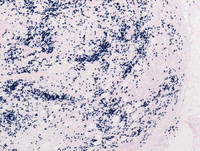

Figure 1: H&E images of breast lump

The low power images demonstrate replacement of breast parenchyma by sheets of large histiocytes and moderate intervening fibrosis admixed with dense lymphoplasmacytic infiltrate. Thick hyalinizing fibrotic band is evident at the periphery of the lesion (image to the left).

Figure 2: H&E images of breast lump

On high power photomicrographs, these infiltrating histiocytes have vesicular nuclei, abundant pale vacuolated cytoplasm and indistinct cell borders. Scattered histiocytes are notable for the presence of engulfed intact lymphocytes and red cells within the cytoplasmic vesicles (Black arrow). This process is known as ‘emperipolesis’, a microscopic hallmark of the entity. Compared to nodal RDD, extranodal RDD often demonstrates more fibrosis and a lesser degree of emperipolesis.